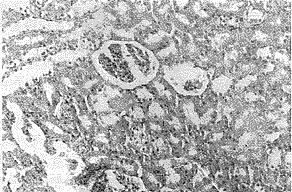

光镜下:烫伤后5小时肾小球和间质均有明显的充血水肿和红细胞渗出,肾小管上皮细胞水肿严重,管内可见蛋白管型(照片1):TRH治疗组这些损伤性病变明显减轻(照片2)。

照片1:NS对照组烫伤后5小时肾小球和间质均有明显

的充血水肿和红细胞渗出,肾小管上皮细胞水肿

严重,管内可见蛋白管型。HE×200